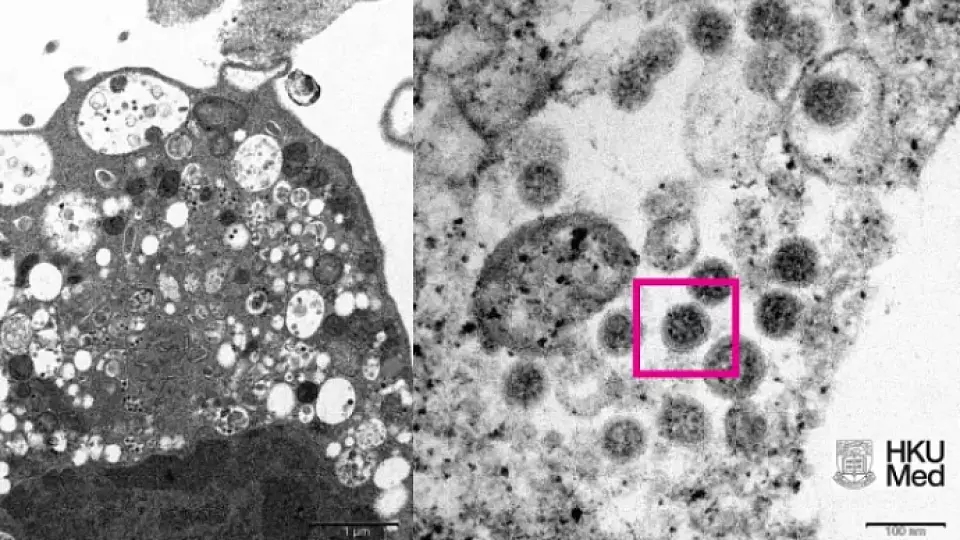

Группа учёных Университета Гонконга с помощью электронного микроскопа получила первое изображение нового штамма «омикрон». Исследователи сфотографировали клетку почки обезьяны, после заражения новым вариантом SARS-CoV-2.

На представленном фото слева при низком увеличении зараженной клетки обезьяны показаны поврежденные клетки с набухшими везикулами, в которых содержатся маленькие чёрные вирусные частицы.

Справа – большее увеличение инфицированной клетки Vero E6, показывающая агрегаты вирусных частиц с шипами в форме короны на их поверхности (в красном прямоугольнике).

Снимок представили клинический профессор кафедры патологии Джон Николс, профессор Малик Пейрис и доктор медицинских наук, профессор кафедры вирусологии Там Ва-Цзин, сообщается на сайте университета.